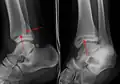

A specialized AP stress view of the ankle is performed when there is concern for an unstable ankle injury. There are two types of stress views: gravity and mechanical.[10] In the gravity stress view, the patient lies in the lateral decubitus position with the ankle dangling over the edge of the table to mimic the mechanical stress view.

AP manual stress view showing a deltoid ligament tear